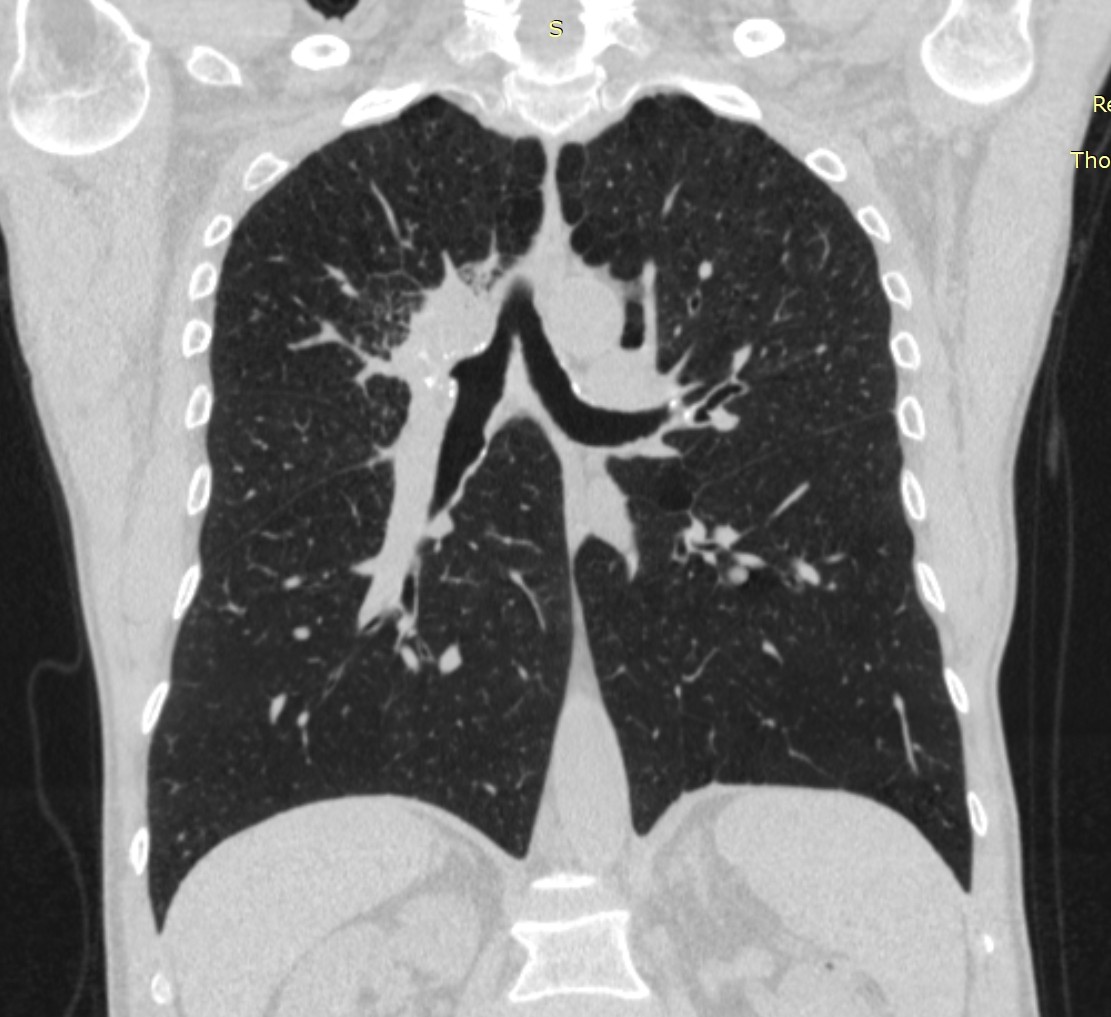

- გულმკერდის კტ კორონარულ ჭრილში 2 თვით ადრე.